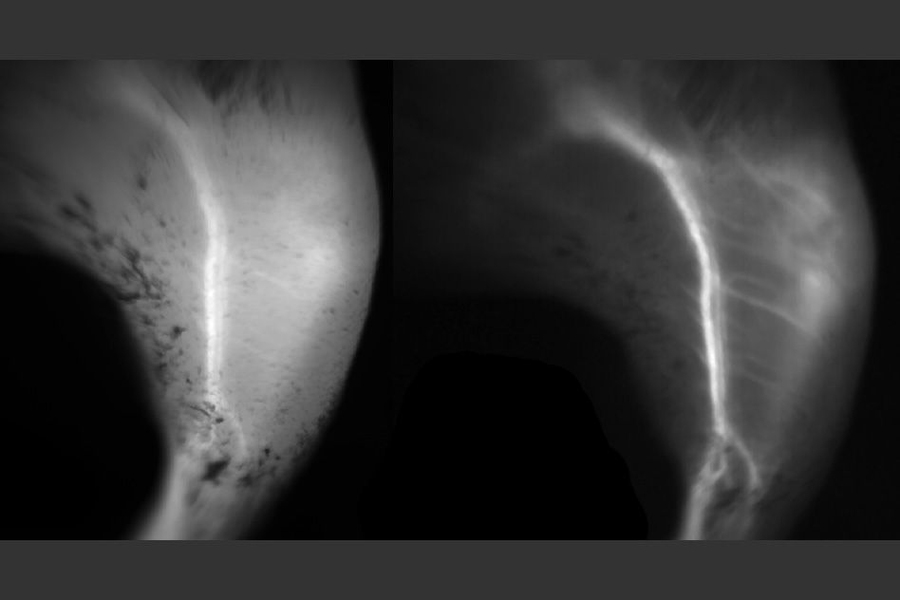

“In the near-infrared, a lot of the features you see in tissue can look foggy, and once you move into the short-wave infrared, the image clears up and everything becomes sharp,” Bruns says.

“We found that short-wave infrared is particularly useful for imaging small objects that are on top of a large background, so when you want to do angiography of small vessels, or capillaries, that’s significantly easier in the short-wave infrared than in the near-infrared,” Franke says.